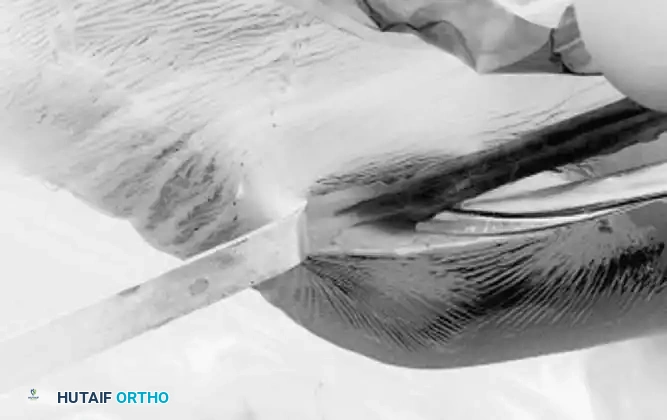

• Begin the technique (Fig. 48-19A) with partial division of the posterior attachment of the meniscal fragment. This can be done with basket forceps, scissors, or an arthroscopic knife. Attempt to cut almost completely through the posterior attachment of the mobile fragment at its junction with the remaining normal meniscal rim (Fig. 48-19B). This cut should not be done blindly to prevent harm to the normal meniscus or articular cartilage or both. Exposure can be aided by passing the arthroscope through the intercondylar notch to look down onto the posterior horn of the meniscus while cutting, or a posteromedial portal can be made if necessary to look directly down onto the meniscus for visualization or to pass through the posterior compartment for cutting of the meniscus.

• Leave a small tag of meniscal tissue intact posteriorly to prevent the meniscus from fl oating freely in the posterior compartment after anterior release.

• Divide the anterior horn attachment with angled scissors, basket forceps, or an arthroscopic knife. Make the release of the anterior attachment fl ush with the intact anterior rim so that no stump or “dog ear” remains (Fig. 48-19C). If the approach is diffi cult from the ipsilateral portal, changing portal sites and approaching from the contralateral portal with the operating instrument often facilitates making this cut. Rarely, a midpatellar portal is necessary so that both anterior portals can be used for instrumentation.

Fig. 48-19 Two-portal technique for bucket-handle tears of lateral meniscus. A, Displaced bucket-handle tear of lateral meniscus probed. B, After reduction of displaced bucket-handle tear, posterior attachment is partially released with scissors. C, Anterior attachment is released with scissors. D, Tenuous remaining posterior attachment is avulsed with grasper and extracted. probe passes into the inferior tear, but not through to the superior surface of the meniscus. Vigorous attempts to hook the probe into an unseen inferior tear should be avoided for danger of extending the tear. If such a tear exists, gentle probing can make the inner border of the meniscus buckle and evert (see Fig. 48-18B). Stable peripheral one-third tears in relatively healthy menisci should be treated by abrasion of the tear site and meniscal synovial tissue to stimulate healing, preserving meniscal function. If stability is in question, suturing may be indicated for most medial meniscal tears (see “Arthroscopic Surgery of the Meniscus” earlier).